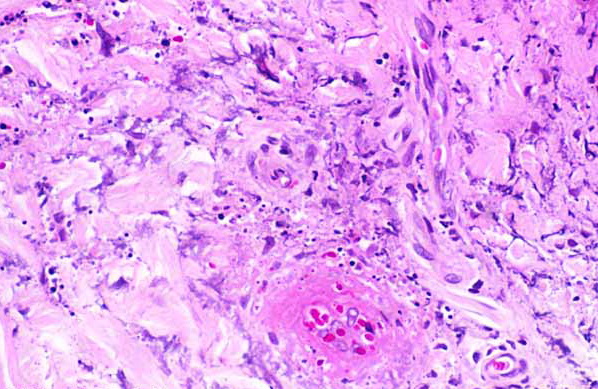

Langerhans cell histiocytosis = كثرة الخلايا الناسجة لانغرهانس

OLYMPUS DIGITAL CAMERA